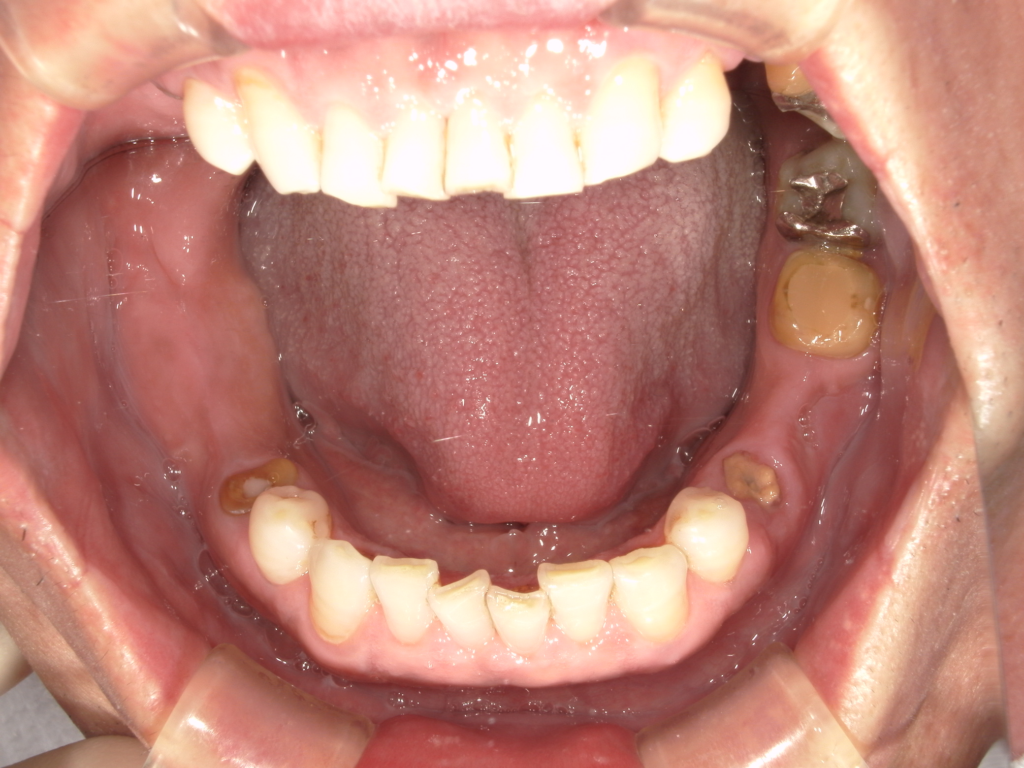

Y様インプラント実例 #44

左の上下の奥歯をインプラントで治療しています。

左下の奥歯は歯を抜くのと同時にインプラントの埋め込みを行っています。

被せものは上下、セラミックスで作っています。

治療前

治療後